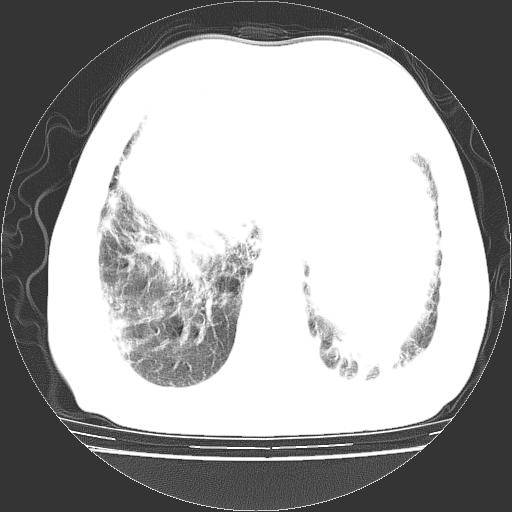

标题: CT25149:男,69岁,反复咳嗽、咳痰五年余,呼吸困难三天。 [打印本页]

男,69岁,反复咳嗽、咳痰五年余,呼吸困难三天。

慢支伴感染、肺气肿、肺心病

慢支伴感染、肺气肿、肺心病!支持!另:间质纤维化!

考虑慢性间质性肺炎并肺间质纤维化。

慢支伴感染、肺气肿、肺心病。双肺间质性改变(间质纤维化)。